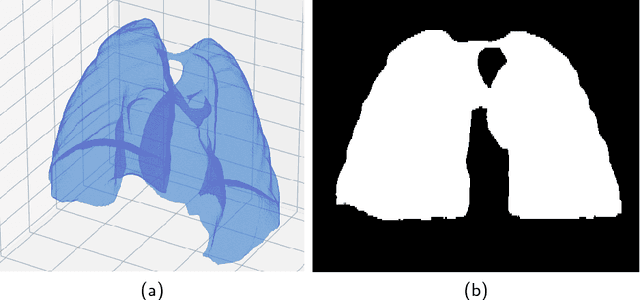

Abstract:The abundance of overlapping anatomical structures appearing in chest radiographs can reduce the performance of lung pathology detection by automated algorithms (CAD) as well as the human reader. In this paper, we present a deep learning based image processing technique for enhancing the contrast of soft lung structures in chest radiographs using Fully Convolutional Neural Networks (FCNN). Two 2D FCNN architectures were trained to accomplish the task: The first performs 2D lung segmentation which is used for normalization of the lung area. The second FCNN is trained to extract lung structures. To create the training images, we employed Simulated X-Ray or Digitally Reconstructed Radiographs (DRR) derived from 516 scans belonging to the LIDC-IDRI dataset. By first segmenting the lungs in the CT domain, we are able to create a dataset of 2D lung masks to be used for training the segmentation FCNN. For training the extraction FCNN, we create DRR images of only voxels belonging to the 3D lung segmentation which we call "Lung X-ray" and use them as target images. Once the lung structures are extracted, the original image can be enhanced by fusing the original input x-ray and the synthesized "Lung X-ray". We show that our enhancement technique is applicable to real x-ray data, and display our results on the recently released NIH Chest X-Ray-14 dataset. We see promising results when training a DenseNet-121 based architecture to work directly on the lung enhanced X-ray images.